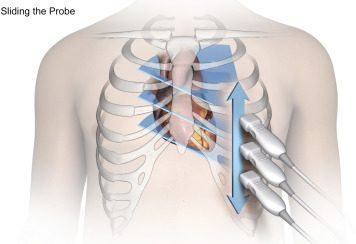

Cửa sổ siêu âm cạnh ức

Mặt cắt trục dài cạnh ức Đầu dò đặt tại bờ trái xương ức với marker hướng lên vai phải của bệnh nhân. |

Cửa sổ siêu âm cạnh ức

Mặt cắt trục dài cạnh ức Đầu dò đặt tại bờ trái xương ức với marker hướng lên vai phải của bệnh nhân. Chùm siêu âm đặt vuông góc với thất trái. |

Cửa sổ siêu âm cạnh ức Mặt cắt trục ngắn cạnh ức Xoay đầu dò 90O từ mặt cắt trục dài cạnh ức và ngửa đầu dò lên trên. |